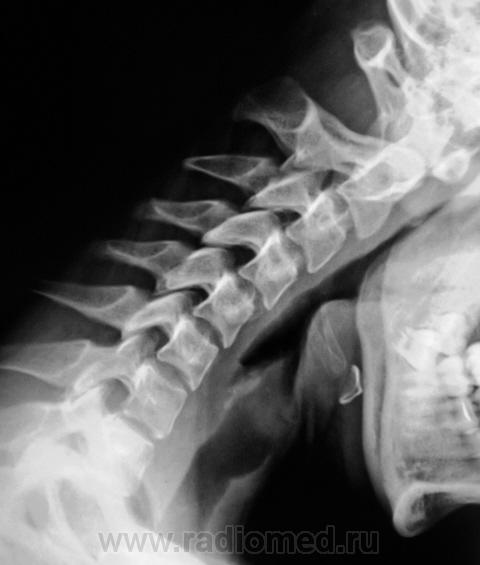

Возможно в СIV-CV  . А функциональные будут?

Появилось сгибание. Похоже - есть.

по мне так нестабильность видится в сегментах С3-С4; С4-С5

Нестабильности нет.

C Cан Санычем  согласен.При функциональных пробах в пределах нормы.

Картина нормы.

Мне подозрителен С4-С5 даже и без сгибания, нет элегантности лордоза.

Было принято такое: если относительное смещение тел позвонков, измеренное со стороны спинномозгового канала, не превышает 2 мм, то эта подвижность в сегментах считается физиологической. Превышение этого показателя расценивалось как нестабильность. Есть работа, в которой рекомендуется вооружиться транспортиром и измерять углы между отвесом и линией, прочерченной по задней поверхности тела позвонка